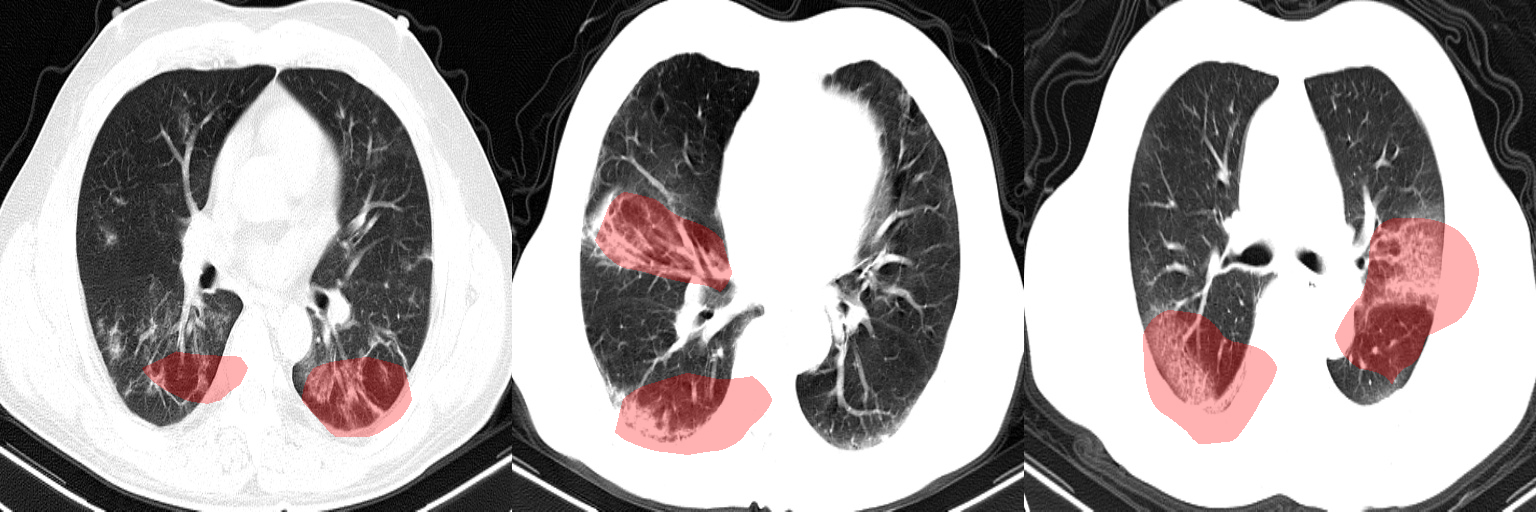

In this study, we leveraged GSInquire [39] to perform explainability-driven performance validation of COVIDNet-CT in order to better understand its decision-making behaviour, and to ensure that its decisions are based on diagnostically-relevant imaging features rather than irrelevant visual indicators. Figure 7 shows the critical factors identified by GSInquire in three chest CT images of patients with COVID-19 pneumonia. Examining these visual interpretations, we observe that COVIDNet-CT primarily leverages abnormalities within the lungs in the chest CT images to identify COVID-19 cases, as well as to differentiate these cases from non-COVID-19 pneumonia cases. As previously mentioned, our initial experiments yielded deep neural networks that were found via explainability-driven performance validation to be basing their detection decisions on irrelevant indicators such as patient tables and imaging artifacts, which highlights the importance of leveraging explainability methods when building and evaluating deep neural networks for clinical applications. Furthermore, the ability to interpret how COVIDNet-CT detects COVID-19 cases may help clinicians trust its predictions, and may also help clinicians discover novel visual indicators of COVID-19 infection which could be leveraged in manual screening via CT imaging.

Figure 7: Example chest CT images of COVID-19 cases and their associated critical factors (highlighted in red) as identified by GSInquire [39].